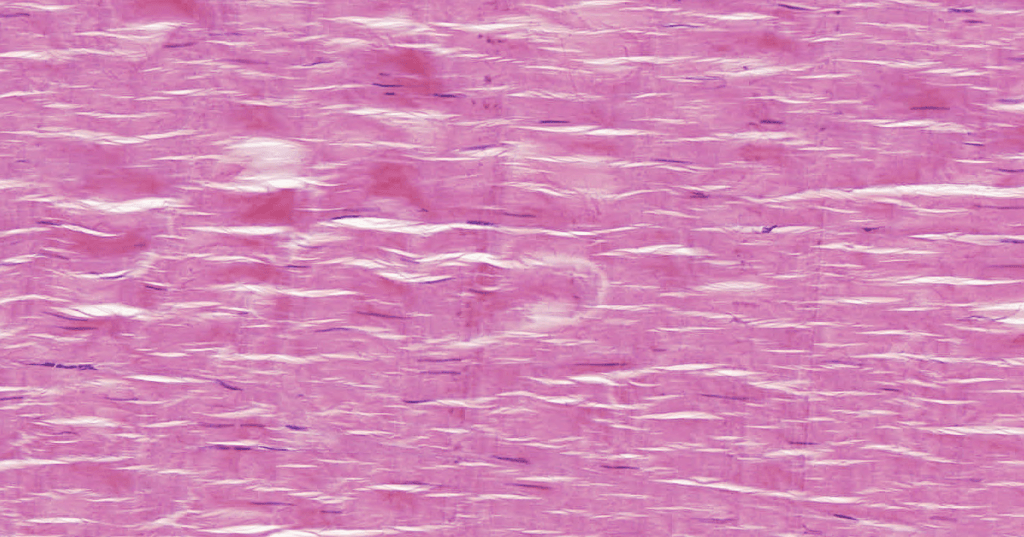

TEJIDO CONJUNTIVO DENSO (TCD)

Forma la cápsula de algunos órganos y se ubica sobre todo en la Dermis reticular. Contiene pocas células y muchas fibras.

REGULAR: fibras con dirección y orientación.